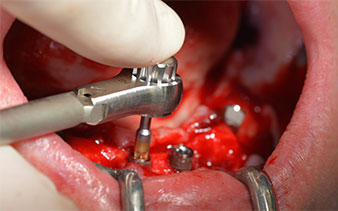

This corresponds to the next preset position in the Implantmed. Here we see the W&H contra-angle handpiece being held at a 45° angle to mesiocaudal in the region of 45 in order to preserve the mental nerve. The mental foramen is used as the anatomic reference for all drilling in this region. The subsequent holes were drilled at a reduced speed of 300 rpm (Fig. 10 and 11).

The next programmed setting is already for placement of the implants. In our practice we usually employ a torque of 32 Ncm to place the implants (Fig. 12 and 13).

High primary stability is an absolute requirement for an immediate restoration. In order to achieve this, the hole was not tapped in this case. The W&H Implantmed drill unit used here is equipped with a suitable special mode for this, which can also be directly selected and is indispensable for many indications. The final revolutions when placing the implants exceeded the value of 32 Ncm and were performed by hand. In such cases, we recommend utilizing the implants’ self-tapping function and twisting the implants backwards and forwards several times. This allows the implant to approach the final position gradually without exerting excessive pressure on the bone (Fig. 14).

Angled abutments (35°) were screwed in to compensate for the divergence of the distal implants, with the result that the emergence profile of all implants was as perpendicular as possible to the bite plane. This is a prerequisite for occlusal placement of the provisional and subsequently the permanent denture (Fig. 15 and 16).